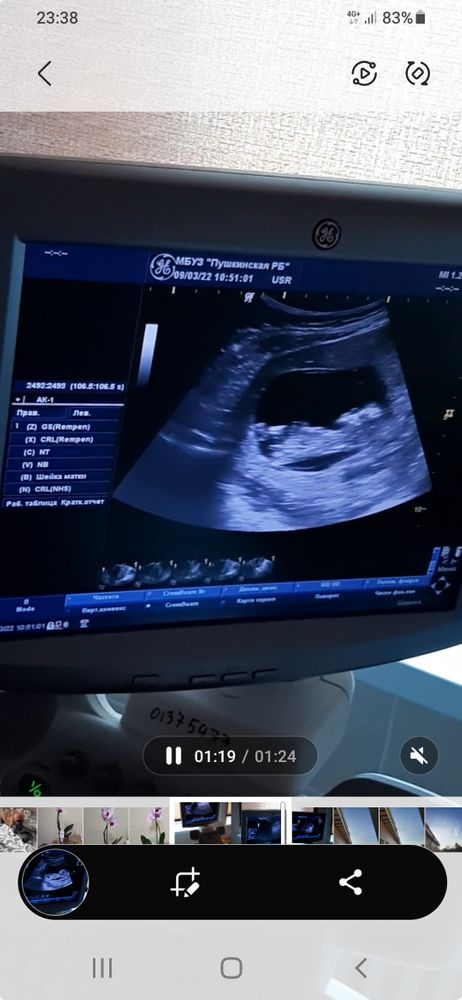

Всем приветик, кто разбирается мальчик или девочка, посмотрите пожалуйста🙏🙏 Изображение Изображение

31.08.2023

Таня Савельева, похоже на девочку)

Natalia, эх хотя бы. Очень хотим дочь, два сына растёт. Дважды на УЗИ сказали, что дочь, а вчера сказали, что сын...

Таня Савельева, ну прям писюшка девчачья по фото ))) Надо чуть позже сделать еще узи )

Таня Савельева, у нас только на 4 раз получилось . ))

Таня Савельева, кто у вас в итоге?)

21.09.2023

Здравствуйте, пока неизвестно. Жду третий скрининг